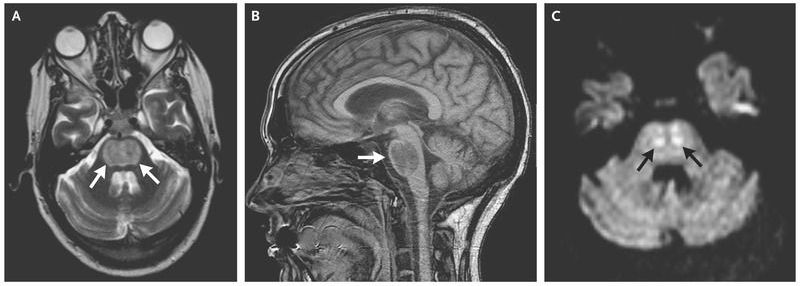

A 35-year-old man presented with acute alcoholic hepatitis and encephalopathy. He was hyponatremic, with a sodium level of 119 mmol per liter. Over the next 5 days his clinical condition improved with supportive treatment, which included lactulose and intravenous vitamins and the careful administration of normal saline for hypovolemia. His serum sodium level gradually increased by approximately 3 mmol per liter per day until reaching 135 mmol per liter. On the sixth day, his level of consciousness declined to a score of 6 on the Glasgow Coma Scale (a scale of 3 to 15, with lower scores indicating reduced levels of consciousness). Findings on computed tomography of the head, performed without the administration of contrast material, were unremarkable. Over the next 2 days, neurologic examination revealed tetraparesis with normal tone. The quadriceps and biceps reflexes were brisk, and the plantar reflex was upward in both feet, but other reflexes were normal. Magnetic resonance imaging of the brain revealed a central area of high T2 (Panel A, arrows) and low T1 (Panel B, arrow) signaling in the pons, with restricted diffusion (Panel C, arrows). These findings are typical in patients with central pontine myelinolysis, or osmotic demyelination syndrome, which typically occurs in response to overly rapid correction of hyponatremia (usually a correction of more than 9 mmol per liter per 24 hours). Clinical features can range from confusion and drowsiness to dysphagia, dysarthria, varying degrees of paresis, and coma or locked-in syndrome. Alcoholism and liver disease predispose patients to central pontine myelinolysis. Our patient subsequently regained the use of his arms and legs slowly over the course of the next year, but bulbar palsy persisted, necessitating permanent placement of a gastrostomy tube for feeding.